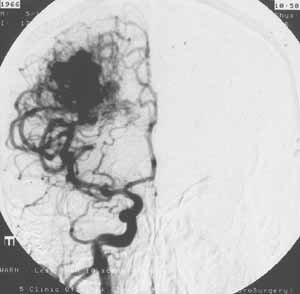

Дигитальная субтракционная ангиография.

Рис. 1 и 2. Артерио-венозная мальформация в правой теменной области, заполняющаяся из передней и средней мозговых артерий. Артериальная фаза. Фронтальная проекция.

(Слева) Классическая ангиограмма. (Справа) Дигитальная субтракционная ангиограмма того же пациента. Изображение костей черепа "стерто". При меньшем расходе контрастного вещества сосудистая сеть видна гораздо лучше.